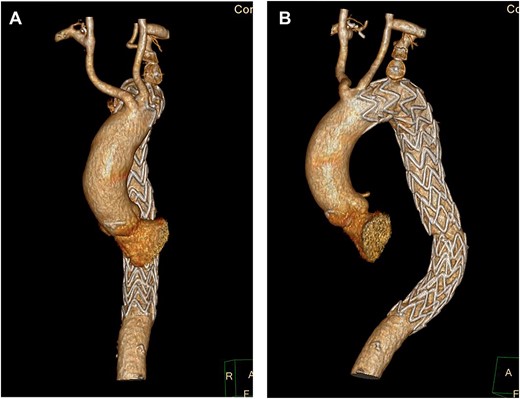

A semi-urgent endovascular thoracic aorta repair (TEVAR, Navion, Medtronic) was performed, with bilateral carotid–subclavian (C-S) bypasses. Intraoperatively, the IMH was noted have progressed to involve the usual mid-segment of the subclavian artery. As a result, a further bypass onto axillary artery was required. She made an uneventful recovery with follow-up imaging at 7 days and 1 month postoperatively showing slow resolution of her IMH and patent bypass grafts (Fig. 2A, B).

(A) 3D-CT reconstruction of extra-anatomical debranching of supra-aortic vessels with bilateral C-S bypasses. (B) 3D-CT reconstruction of thoracic endovascular repair.